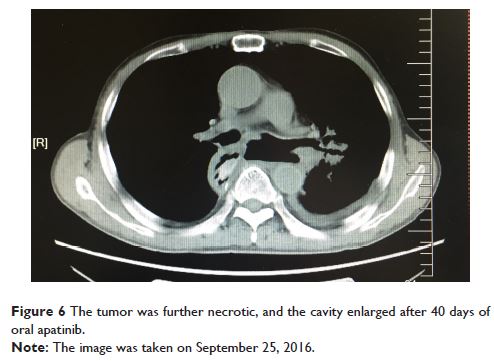

Case Report

- 作者:Hong Tang, Hongyan Wang, Shaoyan Xi, Chunyu He, Yuxi Chang, Qiming Wang, Yufeng Wu

- 期刊:OncoTargets and Therapy